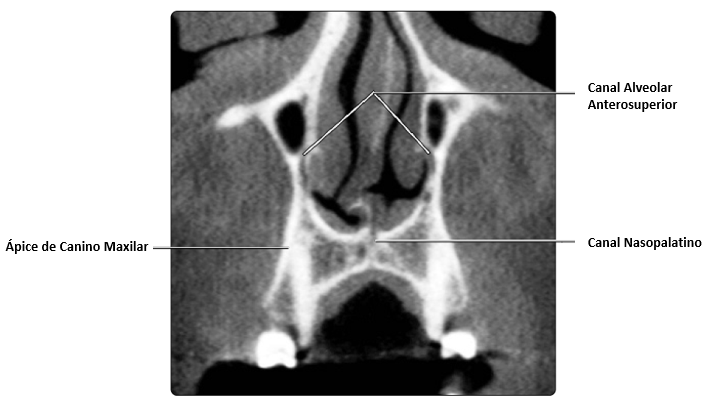

En esta vista coronal de CBCT se muestra el canal alveolar anterosuperior después de que este sale del canal infraorbitario y desciende a lo largo de la pared lateral de la cavidad nasal. La trayectoria de este nervio normalmente pasa cerca de los ápices de los caninos maxilares.